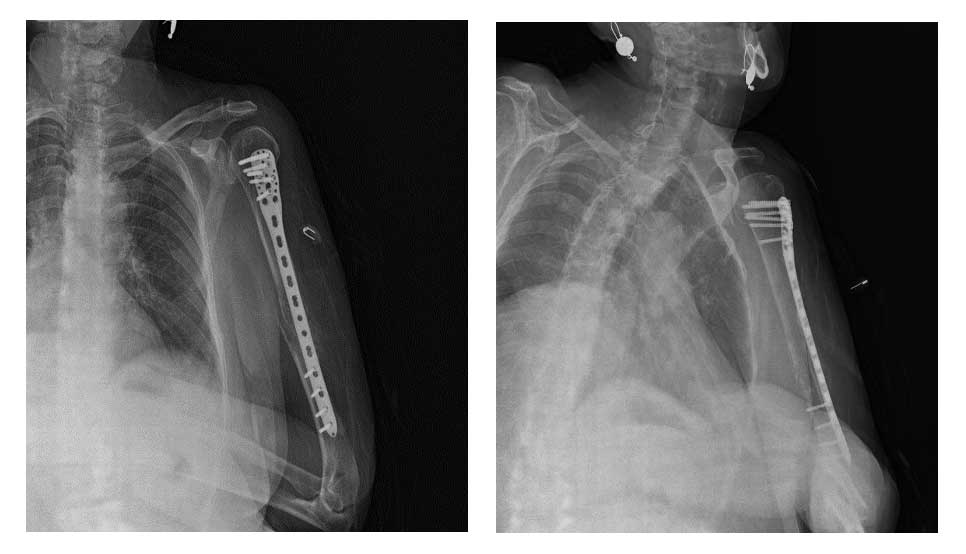

Vaka 5: Meme Kanseri Sol Kol (Humerus) Kemiği Metastazına Bağlı Kırık

Hastaya sol humerus metastazına bağlı gelişen kırık nedeniyle kapalı yerleştirme ve plaklama (internal fiksasyon) işlemi başarıyla uygulandı. Cerrahiyle hem kemik stabilitesi sağlanmış hem de ağrı kontrol altına alınmıştır.

Ameliyat sırasında ve sonrasında herhangi bir komplikasyon gelişmemiştir. Hasta ameliyat sonrası dönemi sorunsuz geçirmiş ve taburcu edilerek radyasyon onkolojisine yönlendirilmiştir.

Ameliyat Sonrası: Anatomik titanyum plak ile fiksasyon uygulanımı görülmekte.